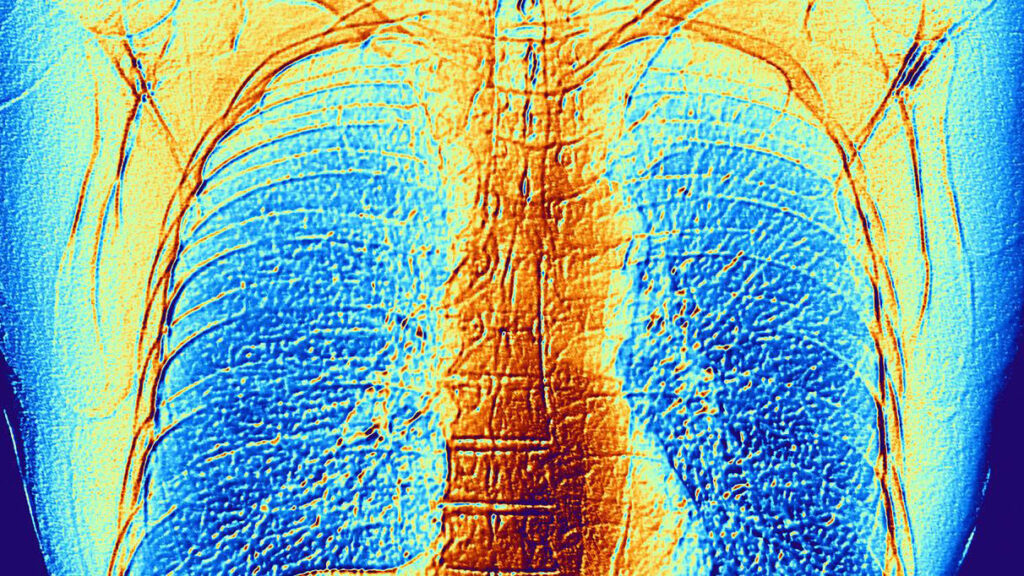

MR images reconstructed from undersampled scans with AI have similar diagnostic value as those reconstructed with conventional methods, find scientists at NYU Langone and Meta AI Research.